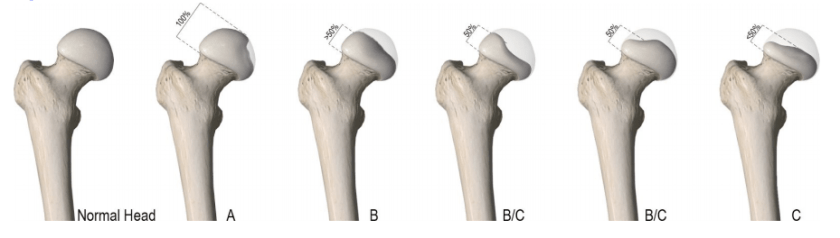

It’s a childhood disorder, which occurs when blood supply is temporarily interrupted to the ball part (femoral head) of the hip joint. Without sufficient blood flow, the bone begins to die and the hip can become intensely inflamed and irritated.

- Stage 4 is when it is ‘healed’. This means the femoral head looks similar to the normal side. However, the key thing here is ‘how’ the bone has grown back, The final shape will then give us a clue as to the long term effects of Perthes. If it grows back as a nice round ball in it’s round socket (and if James hasn’t had any operations along the way), in 5- 6 years, he might return to normal activities, and have a normal walk. If it doesn’t, he is likely to be prone to degenerative arthritis and/or need a hip replacement as a young adult. Surgical intervention could leave him with one leg shorter than the other which may leave him with a certain gait.